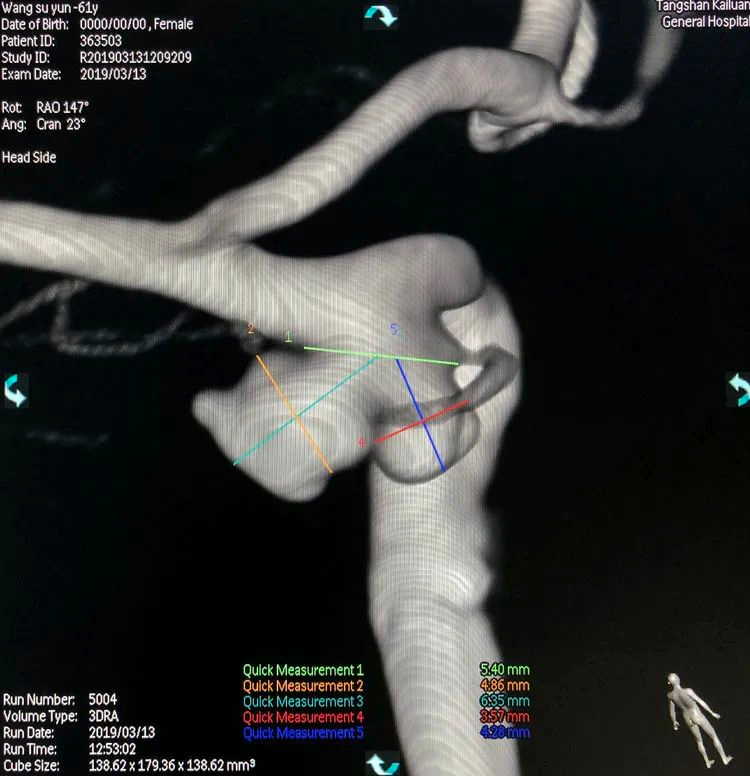

测量,公共瘤颈宽5.40 mm,大分叶4.86 mm×6.35 mm,小分叶3.57 mm×4.28 mm,可视为两个孤立的小型动脉瘤,分而治之: